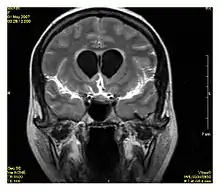

Neuroimaging

MRI is the investigative tool of choice for neurological cancers over CT, as it offers better visualization of the posterior cranial fossa, containing the brainstem and the cerebellum. The contrast provided between grey and white matter makes MRI the best choice for many conditions of the central nervous system, including demyelinating diseases, dementia, cerebrovascular disease, infectious diseases, Alzheimer's disease and epilepsy.[20][21][22] Since many images are taken milliseconds apart, it shows how the brain responds to different stimuli, enabling researchers to study both the functional and structural brain abnormalities in psychological disorders.[23] MRI also is used in guided stereotactic surgery and radiosurgery for treatment of intracranial tumors, arteriovenous malformations, and other surgically treatable conditions using a device known as the N-localizer.[24][25][26] New Artificial intelligence in healthcare tools have demonstrated higher image quality and morphometric analysis in neuroimaging with the application of a denoising system.[27]